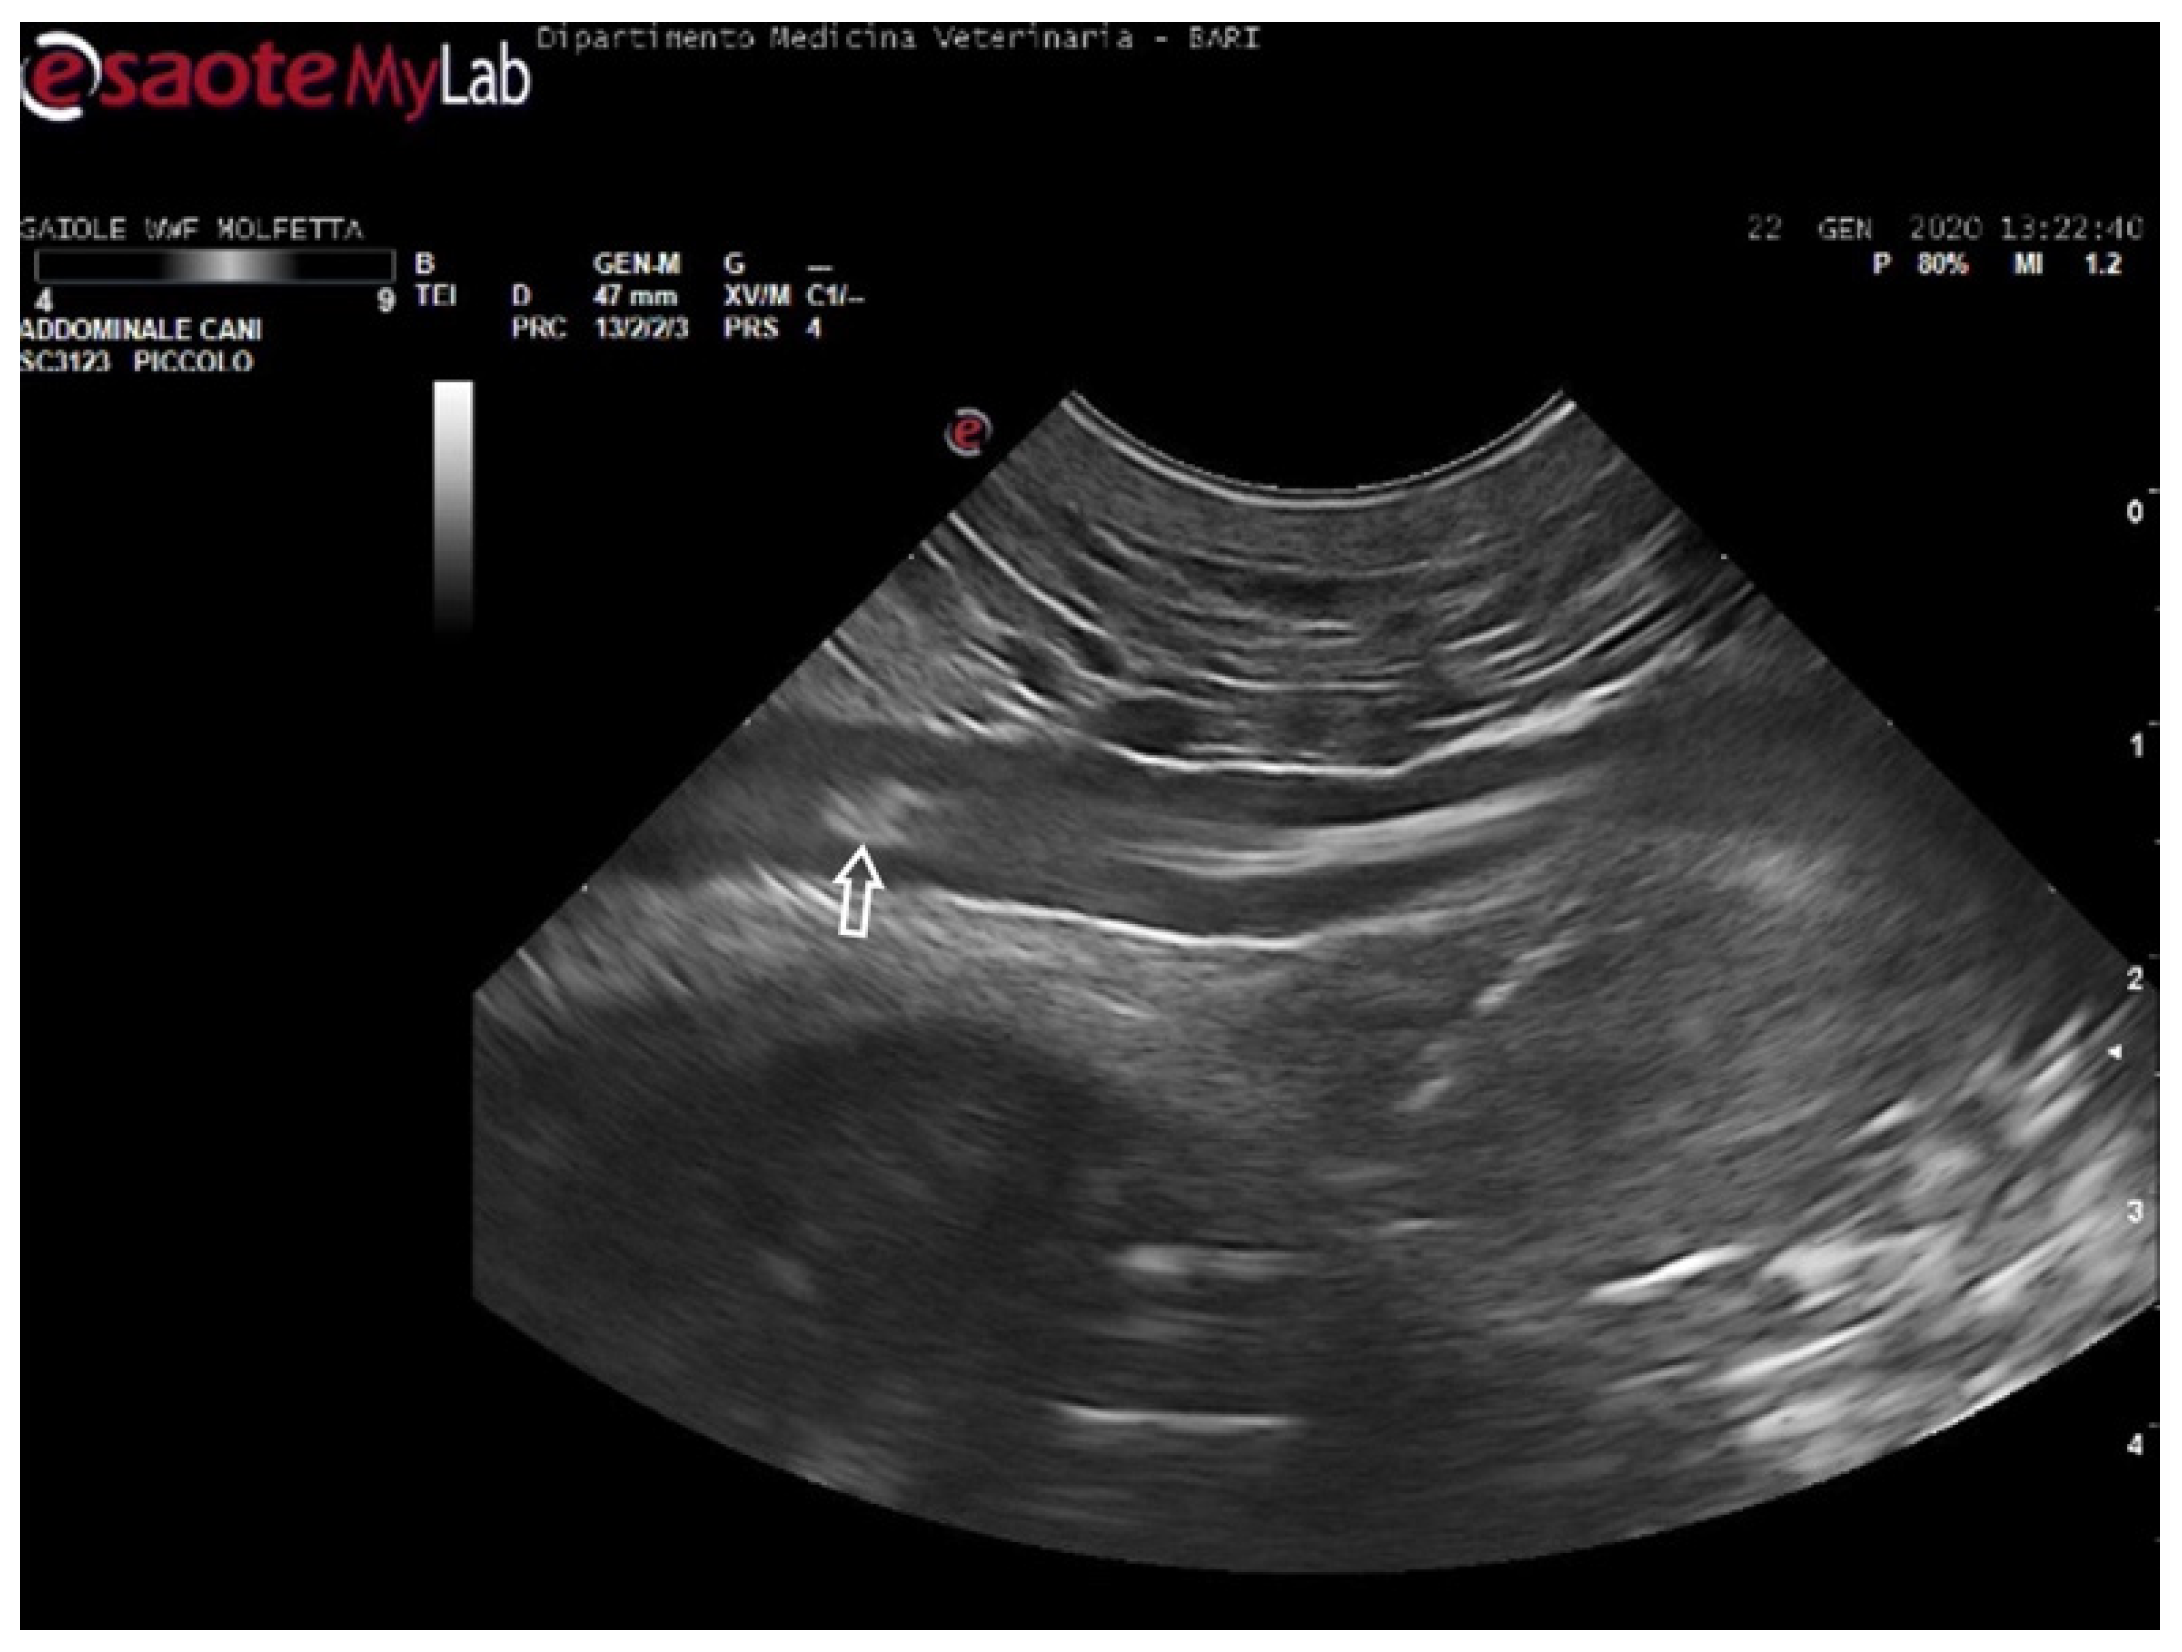

During the ultrasound examination of the seven animals in which no emboli were detected, all the accessible vessels through the acoustic windows were clearly visualized. Blood flow was easily detectable with Color Doppler. From both prefemoral acoustic windows, the renal and iliac arteries were easily distinguishable, along with their blood flow (Figure 4).

Figure 4. Ultrasound scan from the left prefemoral window reveals normal vascular flow within the iliac artery (the white arrow indicating its wall).